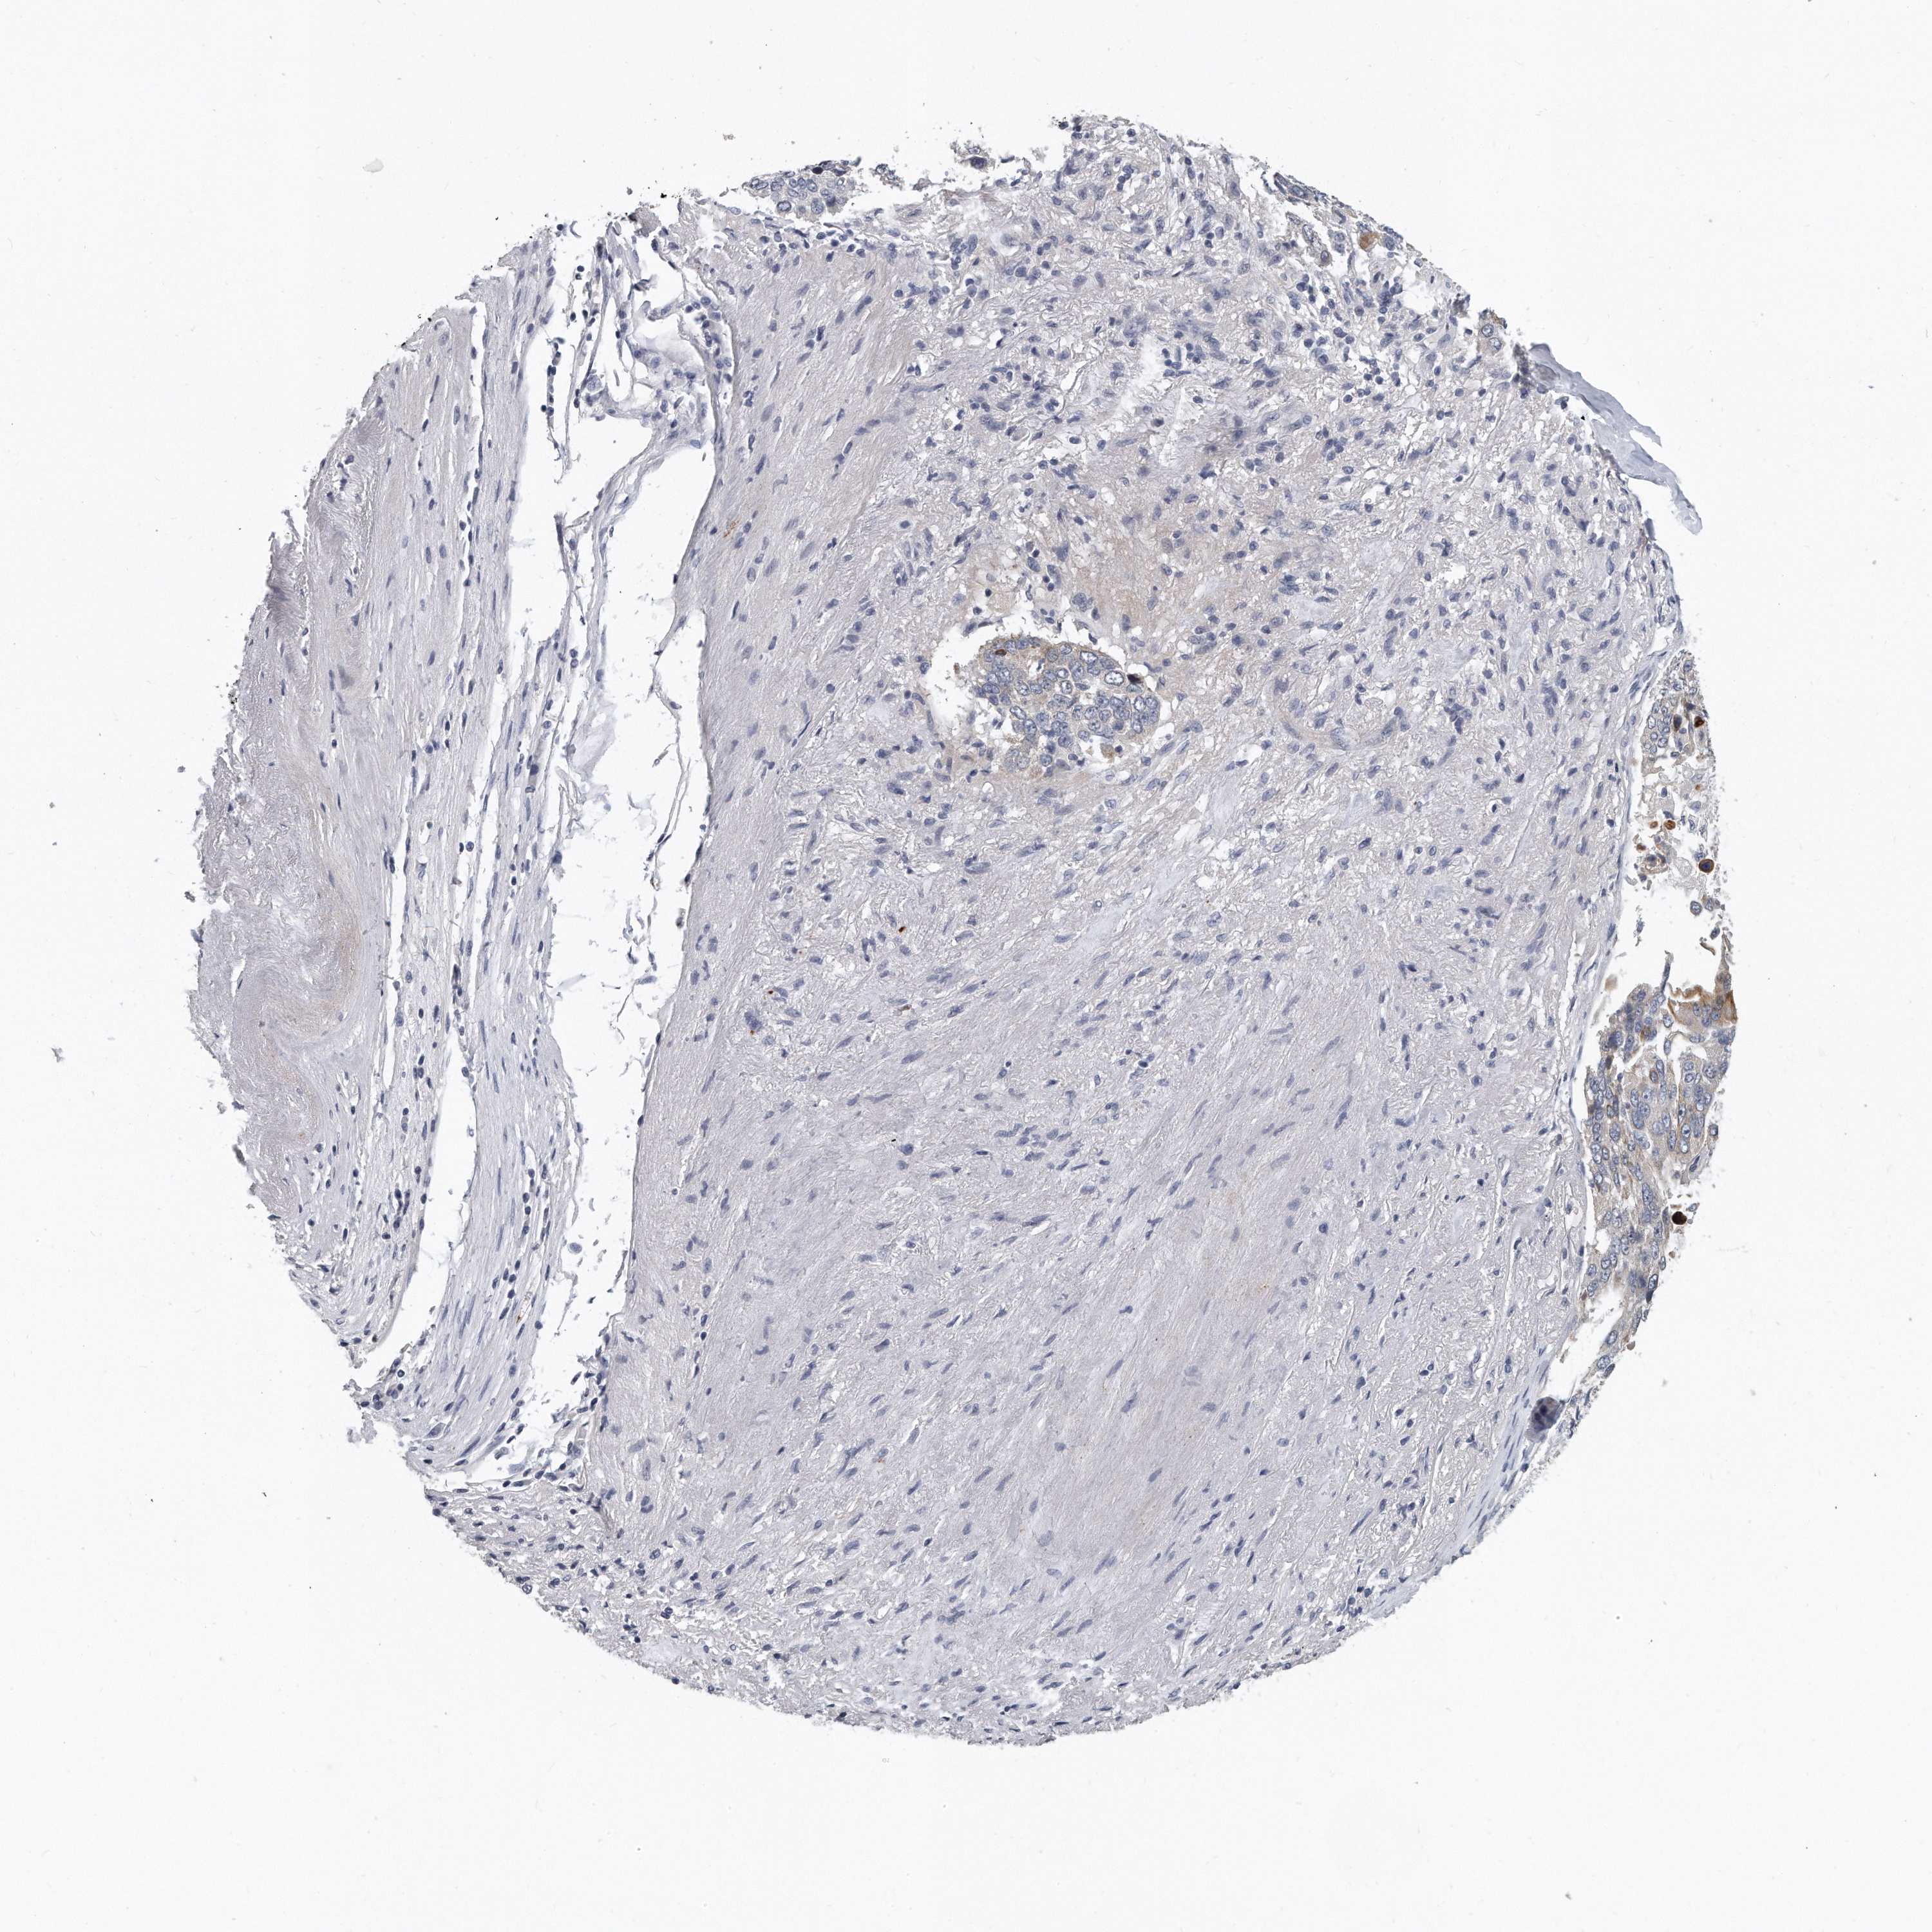

CANCER LUNG CANCER Show tissue menu

Lung cancer

Human cancer

Lung adenocarcinoma

Lung squamous cell carcinoma